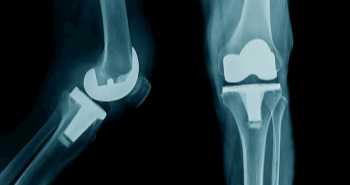

В период с 2006 по 2016 год в исследовании приняли участие 16 пациентов с прогрессирующим остеоартрозом и инфекцией коленного сустава.  В среднем пациенты находились под наблюдением в течение 6,1 года. Все пациенты ранее перенесли одно или несколько неудачных артроскопических или открытых вмешательств. Всем пациентам был установлен один и тот же самодельный артикулирующий спейсер с добавлением антибиотиков (см. рисунок).

Рисунок. После радикального дебридмента был создан артикулирующий спейсер из металлопластика (а) с использованием элемента протеза бедренной кости, заднестабилизированного полиэтиленового вкладыша (NexGen Legacy PosteriorStabilized Knee LPS, Zimmer, Варшава, США) и цемента с добавлением антибиотиков (1 г гентамицина + 1 г клиндамицина на 40 г цемента) (b). Спейсер обеспечивает отличную амплитуду движений и высокую местную дозу антибиотиков в суставе.